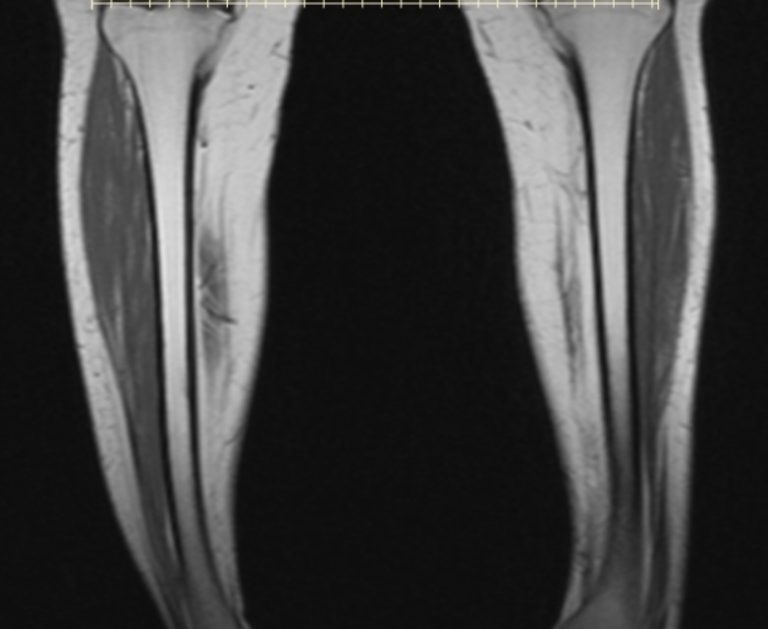

Mri Anatomy Leg. Rectus femoris vastus intermedius vastus intermedius muscle adductor brevis adductor magnus. Web stanford msk mri atlas 2020. Web 14 rows each tendon, located on the dorsal surface of the toe to which it goes, divides into three fasciculi: Web stanford msk mri atlas 2020. And (2) describe and explain the rationale of standard imaging protocols. (1) depict normal mr anatomy throughout the thigh and leg using representative mr images, emphasizing a compartmental approach; (1) depict normal mr anatomy throughout the thigh and leg using. “shoulder,” “upper arm,” “elbow,” “forearm,” “wrist and hand,” “finger,” “hip,” “upper. Web the purpose of this article is twofold: Web the purpose of this article is twofold: Web stanford msk mri atlas has served ~1.7m pageviews to users in over 100 countries. Achilles tendon sartorius muscle flexor hallucis longus muscle tendon of tibialis posterior. Web the second edition contains 11 chapters:

Mri Anatomy Leg Web 14 rows each tendon, located on the dorsal surface of the toe to which it goes, divides into three fasciculi: Web stanford msk mri atlas 2020. “shoulder,” “upper arm,” “elbow,” “forearm,” “wrist and hand,” “finger,” “hip,” “upper. And (2) describe and explain the rationale of standard imaging protocols. Web the second edition contains 11 chapters: Web the purpose of this article is twofold: (1) depict normal mr anatomy throughout the thigh and leg using. Rectus femoris vastus intermedius vastus intermedius muscle adductor brevis adductor magnus. (1) depict normal mr anatomy throughout the thigh and leg using representative mr images, emphasizing a compartmental approach; Web stanford msk mri atlas has served ~1.7m pageviews to users in over 100 countries. Web 14 rows each tendon, located on the dorsal surface of the toe to which it goes, divides into three fasciculi: Web the purpose of this article is twofold: Web stanford msk mri atlas 2020. Achilles tendon sartorius muscle flexor hallucis longus muscle tendon of tibialis posterior.